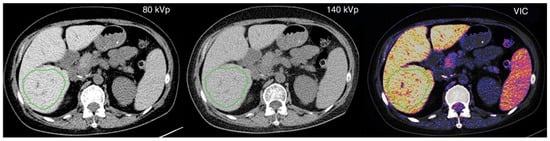

2.1. Dual-Energy CT

- Luo, X.F.; Xie, X.Q.; Cheng, S.; Yang, Y.; Yan, J.; Zhang, H.; Chai, W.M.; Schmidt, B.; Yan, F.H. Dual-Energy CT for Patients Suspected of Having Liver Iron Overload: Can Virtual Iron Content Imaging Accurately Quantify Liver Iron Content? Radiology 2015, 277, 95–103. [Google Scholar] [CrossRef]

- Joe, E.; Kim, S.H.; Lee, K.B.; Jang, J.-J.; Lee, J.Y.; Lee, J.M.; Han, J.K.; Choi, B.I. Feasibility and accuracy of dual-source dual-energy CT for noninvasive determination of hepatic iron accumulation. Radiology 2012, 262, 126–135. [Google Scholar] [CrossRef]